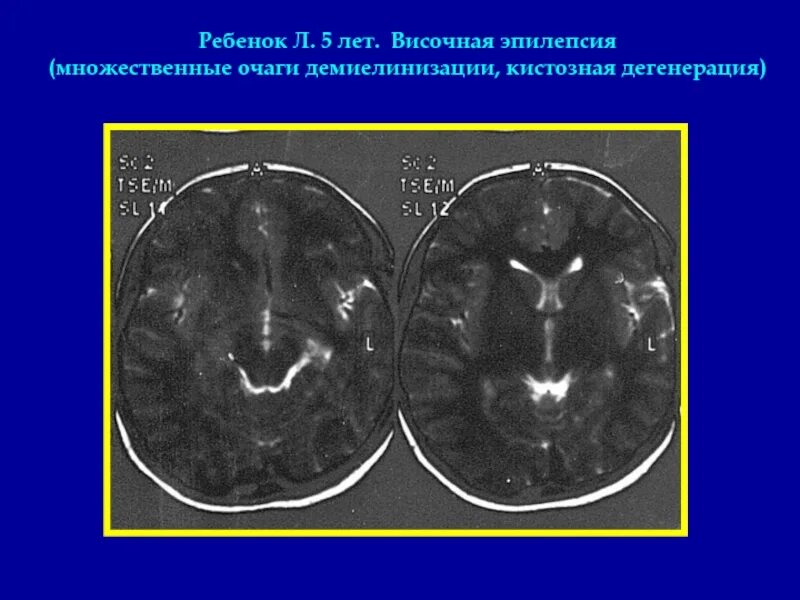

Приступы височной эпилепсии